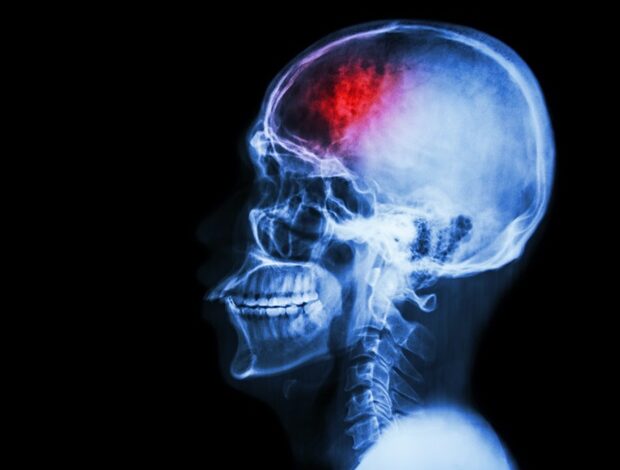

Delirium, běžně pozorované u kriticky nemocných pacientů po intracerebrálním krvácení (ICH), je akutní neuropsychiatrická porucha charakterizovaná poruchami pozornosti, vědomí a kognice. Základní mechanismy mozkové sítě zůstávají špatně pochopeny. Tato studie si kladla za cíl prozkoumat funkční konektivitu (FC) ascendentního retikulárního aktivačního systému (ARAS) u pacientů s deliriem s ICH bazálních ganglií a identifikovat potenciální biomarkery pro predikci nástupu deliria.

U pacientů s ICH s deliriem byla pozorována významná porucha FC mezi jádry ARAS mozkového kmene a levým parahipokampálním gyrem. Síla FC mezi těmito oblastmi byla spolehlivým prediktorem výskytu deliria s plochou pod křivkou 0,893, což ukazuje na vysokou přesnost predikce.

Narušení FC mezi jádry ARAS mozkového kmene a levým parahipokampovým gyrem může být základem patogeneze deliria. Odpovídající síla FC by mohla sloužit jako efektivní biomarker pro předpovídání nástupu deliria. Obnovení normální konektivity mezi těmito regiony má potenciál jako strategie pro brzké zvrácení deliria a představuje klíčové zaměření budoucího výzkumu.